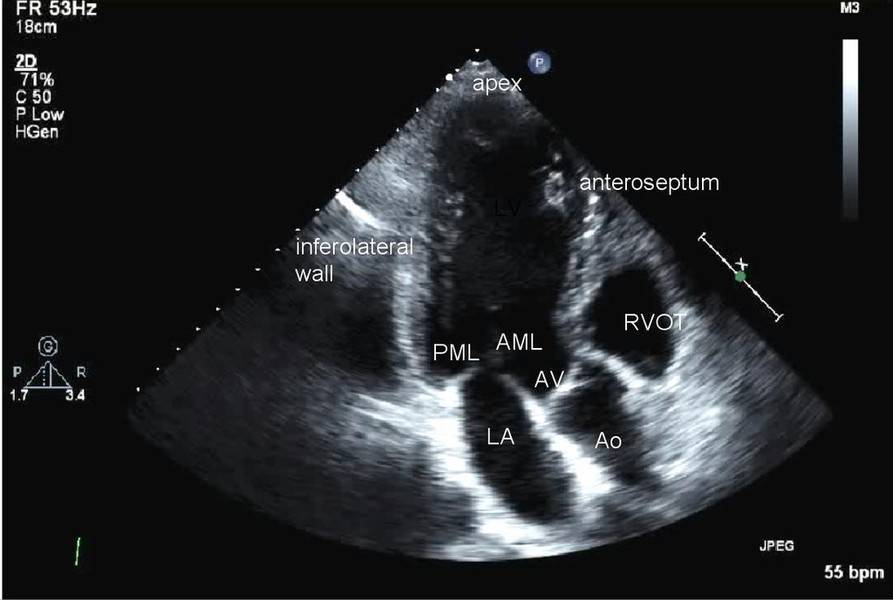

پیش از آنکه بررسی کنیم چه زمانی اکو قلب لازم است؟ بهتر است که با این آزمایش بیشتر آشنا شویم.اکوکاردیوگرافی یا اکو یکی از تست های قلبی است. این اسکن به منظور مشاهده قلب و رگ های خونی مجاور آن به کار می رود. به عبارتی می توان گفت اکوی قلب نوعی اسکن سونوگرافی می باشد و در آن یک پروب کوچک جهت ارسال امواج صوتی با فرکانس بالا وجود دارد. هنگامی که این امواج به بخش مورد نظر در بدن برخورد می کنند و باز می گردند پژواک هایی را ایجاد می نمایند. پروب با جمع آوری این پژواک ها در زمان تصویربرداری آن ها را به شکل تصویر متحرک روی صفحه نمایشگر تبدیل می کند. لازم به ذکر است که اکو قلب در بیمارستان یا کلینیک توسط متخصص قلب (کاردیولوژیست) و یا تکنسین آموزش دیده سونوگرافی انجام می شود. دقت داشته باشید که اکو قلب و نوار قلب با وجود تشابه اسمی که با یکدیگر دارند کاملا متفاوت هستند.

اکوکاردیوگرافی از امواج صوتی برای ایجاد تصاویر قلب استفاده می کند. این آزمایش رایج می تواند جریان خون را از طریق قلب و دریچه های قلب نشان دهد. متخصص مراقبت های بهداشتی شما می تواند از تصاویر این آزمایش برای یافتن بیماری قلبی و سایر بیماری های قلبی استفاده کند.